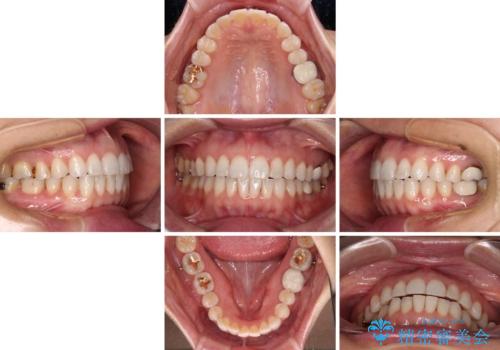

ちょっとしたデコボコをしっかりと改善したい インビザライン矯正

デコボコはあっという間に解消されましたが、上下前歯の隙間がなかなか解消されませんでした。

飲み込みの際に舌を前方に突出する癖があり、飲み込みの度に前歯に強く接触していたため、上下前歯の隙間が維持されていました。

舌の訓練を徹底していただいたことで、徐々に隙間は解消され、きれいな歯列に整えることができました。